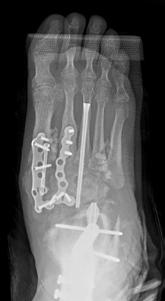

To illustrate the pitfalls of CN treatment, we have presented a 61-year-old male who already underwent midfoot fusion for prior Charcot event (Figure 2). He comes in for a second opinion and declined an ankle fusion and wanted to preserve his motion so that he could drive. The second set of radiographs demonstrate attempted hindfoot fusion that resulted in collapse to the talus bone in the ankle joint (Figure 3). Recent podiatric research shows an alternative treatment option to the traditional rigid fixation. The Charcot flipper foot construct involves fusing the hindfoot while leaving the midfoot mobile to allow for motion to lower risk of further breakdown (2). The final surgery was performed to replacing the dislocated talus with a cadaver bone and fusing the hindfoot with an intramedullary nail all through small incisions for preparation and hardware fixation. The

midfoot screws that were added in his second surgery were removed and an osteotomy was created to allow for the forefoot to move in the sagittal plane (Figure 4).

Figure 4. Final surgery resulting in plantigrade foot by fusing the entire hindfoot and unlocking the midfoot to allow for active plantarflexion of the forefoot (dotted line). The talus was replaced with a cadaver bone. Previous ulceration on the lateral ankle healed uneventfully.